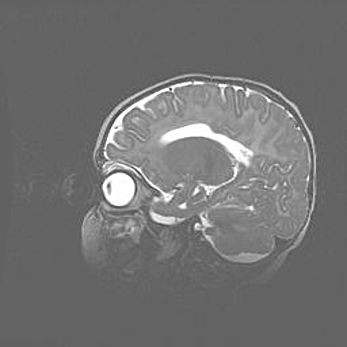

Мальформация Денди-Уокера. Киста задней черепной ямки.

Агенезия мозолистого тела.

Возраст: 2,5 месяца

Вес: 2420 г

Пол: женский

Окружность головы: 37 см

Срок гестации: 32 недели

Мальформация Денди—Уокера — редкий вид патологии ЦНС, представляющий собой врожденный порок развития каудального отдела ствола и червя мозжечка, ведущий к неполному раскрытию срединной (Мажанди) и латеральных (Лушка) апертур IV желудочка мозга. Для этогно синдрома характерна триада симптомов: гипотрофия червя мозжечка и/или полушарий мозжечка, кисты задней черепной ямки, гидроцефалия различной степени. В 70% случаев порок сочетается и с другими аномалиями головного мозга, в частности с агенезией мозолистого тела.